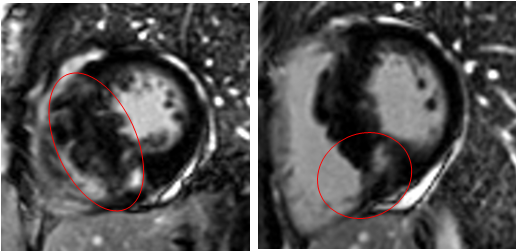

Liwen术式病例介绍

T波: Ⅰ Ⅱ ⅢaVF V3-V6 倒置

|作者:李静 刘丽文

|单位:空军(第四)军医大学西京医院